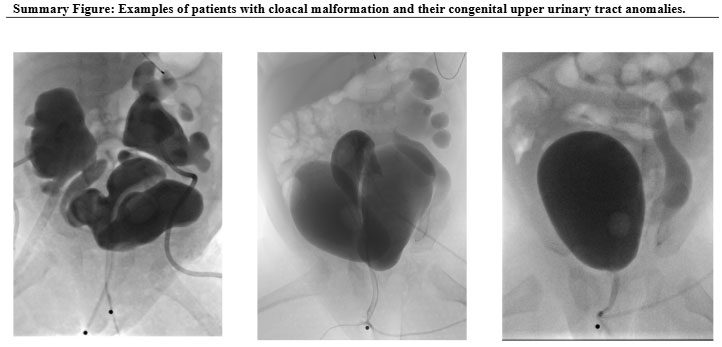

Some key successes include the development of innovative surgical procedures for conditions such as imperforate anus and anorectal malformations, advanced repair techniques for cloacal malformations, integrated care strategies for colonic dysmotility, and novel approaches for the newborn care of patients with cloacal exstrophy. All these new approaches were developed at Children’s National over the past five years.